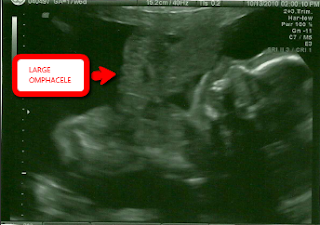

Findings: U/S shows large anterior midline thoraco-abdominal wall defect with ectopia cordis and large ompahlocele. The spine has the appearance of severe scoliosis and extreme curvature in the thoracic portion, suggesting kyphosis. The amniotic fluid is quite generous at 26.4cm. The umbilical looked extremely short, but precise length measurement could not be obtained. Fetus showed little to NO movement. Follow up MRI confirmed the following:

4. Large omphalocele (containing liver, stomach, spleen, and almost all of the bowel) By MRI, omphalocele appears to be contiguous with the uterine wall (This is a very important finding that could not be determined with Ultrasound).